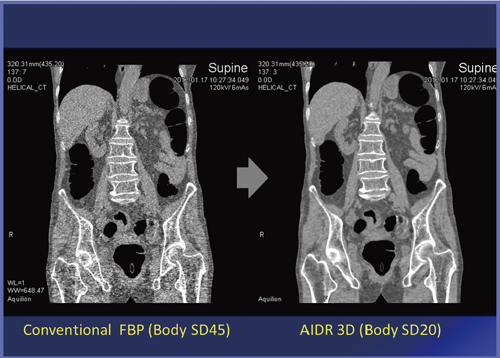

被ばく低減の新技術として最近,“AIDR 3D”などの逐次近似再構成法を応用した低線量撮影が注目されている。

AIDR 3Dの有無でCTCの画像を比較すると,AIDR 3Dなしの場合はノイズが強く,評価が難しくなることがわかる(図2)。

図2 AIDR 3Dの有無によるノイズの差